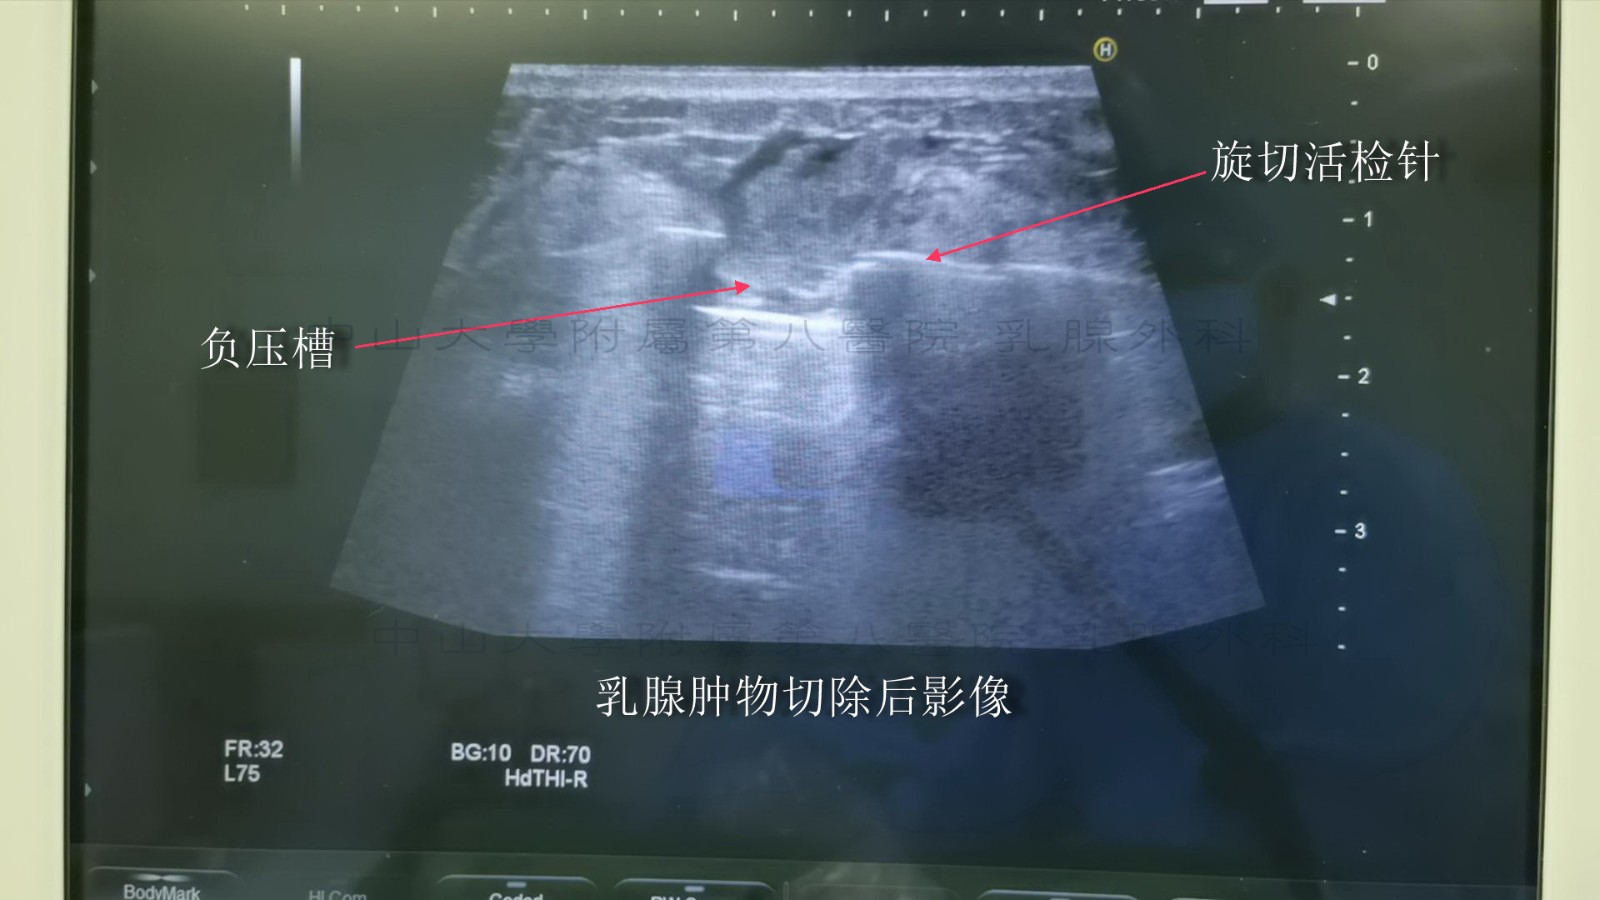

真空辅助乳腺活检(vacuum-assisted breast biopsy,VABB)系统是影像学引导的乳腺活检系统,由真空泵和旋切刀组成。旋切刀通常采用中空管腔设计,所带有的凹槽通过负压吸住待切除部位并完成旋切过程。真空装置由电脑控制保持负压抽吸乳腺病灶,进行旋转切割;通过标本运送系统将切取的标本运出体外。全部操作通过单次穿刺就能准确、简便地收集多个连续样本。超声引导下VABB 是一种多数在局部麻醉下进行的微创手术,皮肤切口仅3~5 mm;在超声定位引导下将活检探针穿过皮肤,到达目标病灶下方;在负压吸引下,将病灶组织吸入旋切刀的收集槽中进行旋切,直到完成拟定的切除操作。整个过程是在高分辨率声像图监控下的可视性操作,其定位准确,操作便利,具有良好的美容效果,可达到临床诊断和治疗的目的,已经成为乳腺外科常用的操作技术。

下图示为对肿物进行旋切(下图可见肿物吸入负压槽中)

下图示为完成旋切后超声再次检查术区

下图示为肿物切除后的残腔